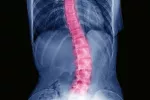

Nuevo kit para diagnosticar escoliosis idiopática del adolescente

La escoliosis idiopática (de origen desconocido) es el tipo de escoliosis más común (el 70-80% de los casos), y además de causar una deformidad estética, el afectado puede tener síntomas como dolor, una limitación funcional, y restricciones de la función pulmonar. Los pacientes deben someterse a exploraciones físicas y pruebas radiológicas para diagnosticar la enfermedad, y para su posterior seguimiento hasta finalizar el desarrollo esquelético, por lo que se exponen a radiaciones continuadas.